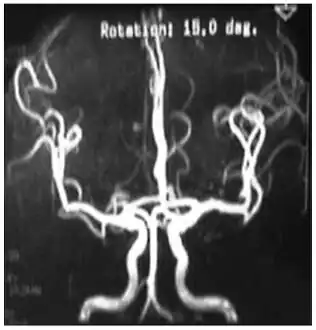

Cerebral vessels by brain MRA show cerebral atherosclerosis (and minor angiostenosis) -

Angio MRI of supra-aortic vessels after the injection of 20cc of gadolinium for contrast